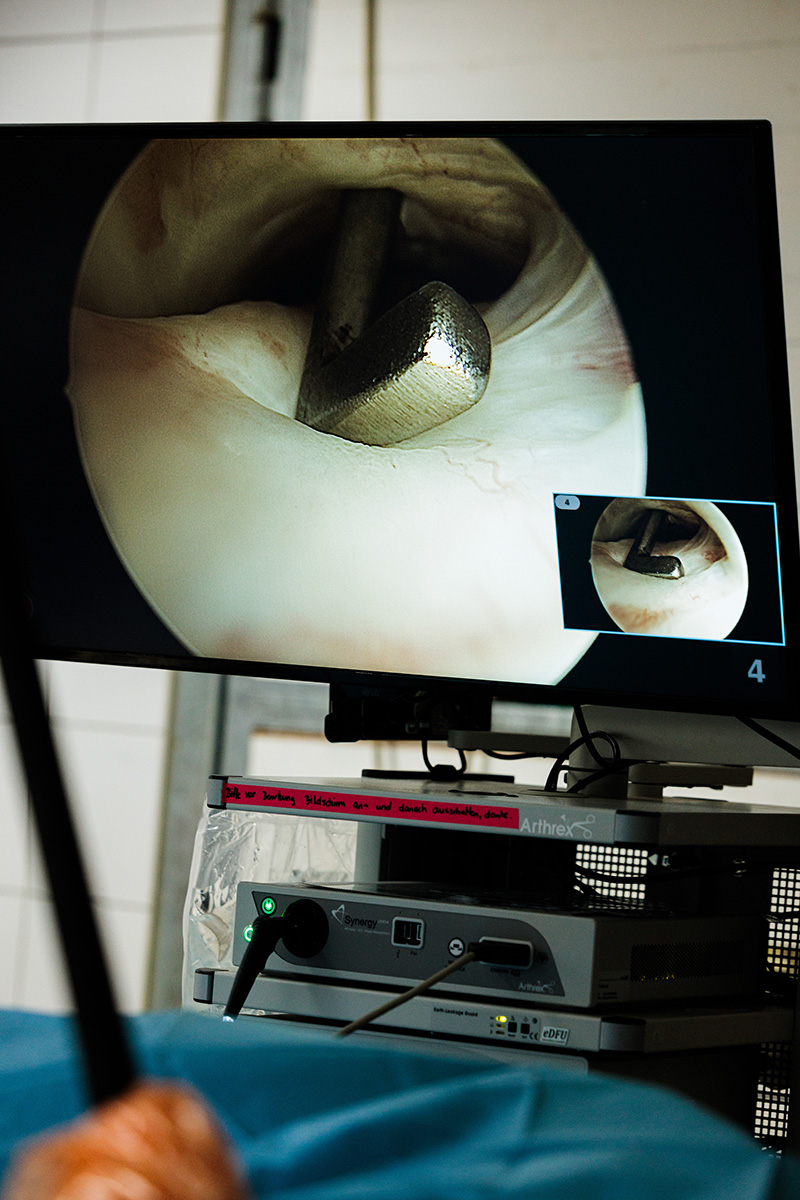

Aus diesem Grund und um die Heilungsphase nach Operationen so komplikationsarm und zügig, wie möglich zu gestalten, ist es uns besonders wichtig, minimalinvasive Operationsmethoden anzuwenden, wo auch immer diese möglich sind. Das gilt sowohl für orthopädische Eingriffe (Arthroskopien, Tendovaginoskopien und oder minimalinvasive Frakturbehandlungen) als auch in der Weichteilchirurgie (Laparoskopien).

Wenn es auf höchste Präzision ankommt: Frakturen von Hufbein oder Strahlbein sowie Frakturen der kleinen Knochen im Sprunggelenk z. B. können bei uns unter CT-Kontrolle operiert werden. Das sorgt für die optimale Positionierung der Implantate bei minimalinvasiven Zugängen zum gebrochenen Knochen

Obwohl die Überwachung von Pferden in Vollnarkose bei uns modernsten Standards folgt, versuchen wir auch hier, wenn immer möglich, Operationen am stehenden, sedierten und nur lokal anästhesierten Patienten durchzuführen. Verschiedene laparoskopische Operationen wie der Verschluss des Milz-Nieren-Raumes oder das Entfernen von Eierstocktumoren bei der Stute sind z. B ohne Vollnarkose möglich. Selbst ausgewählte Arthroskopien und Operationen an den oberen Atemwegen (z.B. LASER-Resektionen des Stimmbandes, Kehlkopfpfeiffer-OP) können bei uns „im Stehen“ operiert werden.